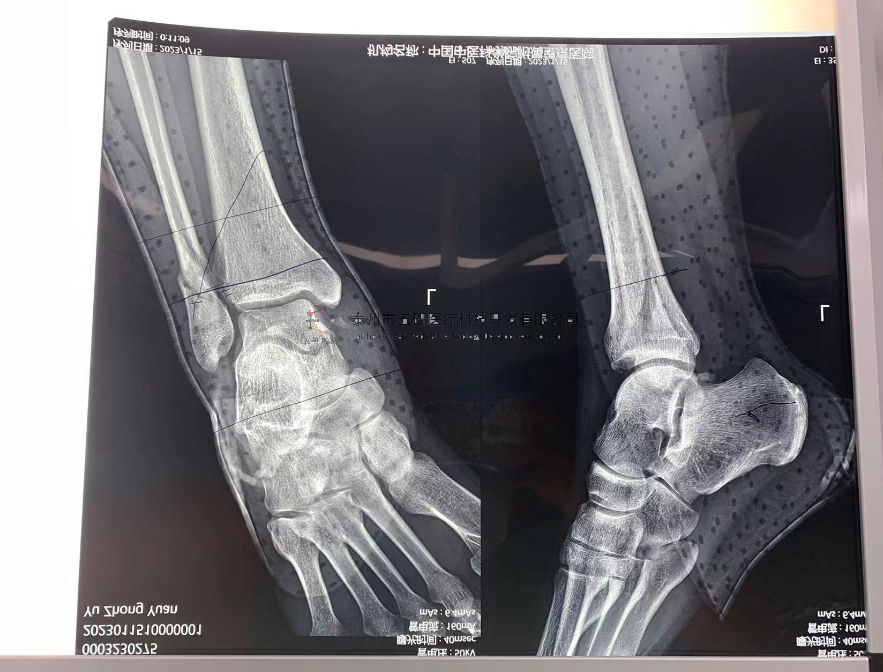

【治療后影像】

【手術(shù)資料】